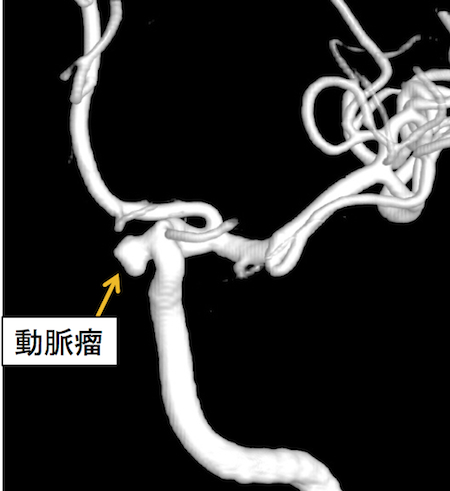

脳動脈瘤とは、脳動脈の血管壁が薄くなることやもろくなることで、そこが膨らみ、血液が入り込んで、コブのような形状になることです。

脳動脈瘤の中には、動脈に流れている血液が常に循環しているため、基本的に脳動脈瘤が自然にしぼんで治癒することはなく、この脳動脈瘤が破裂すると、くも膜下出血を発症します。

しかし、脳動脈瘤は必ず破裂するわけではありません(未破裂脳動脈瘤)。未破裂脳動脈瘤はほとんどが無症状であり、脳ドックや検査などで偶然に発見されるケースが多く、破裂せずに一生を過ごす方もいらっしゃいます。

一方、脳動脈瘤が破裂し、くも膜下出血を発症すると、今までに経験したことが無いような激しい頭痛が起こり、嘔吐や意識障害も同時に起こります。